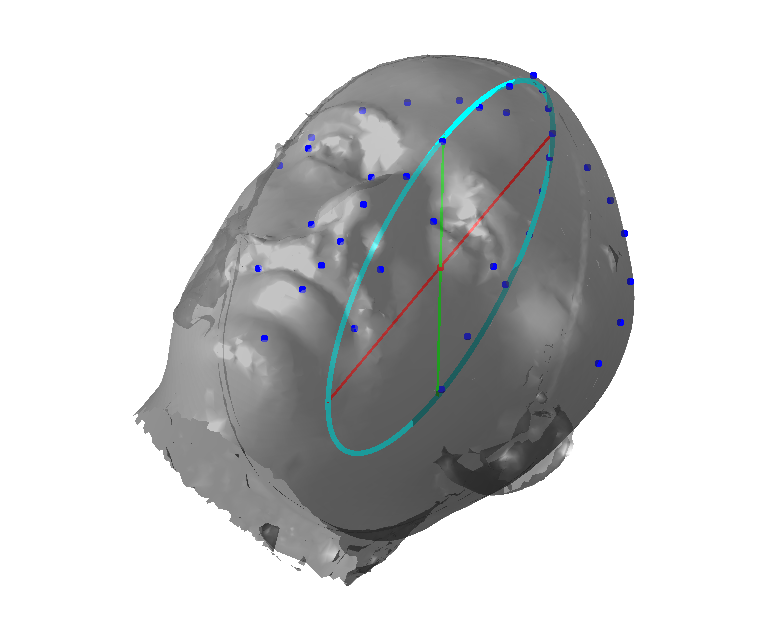

5.8 Ellipse fitting

Ellipse fitting was motivated by the fact that large sections of the cranium appeared to be elliptical in form, thus suggesting a natural centre and frame origin with which to model cranial shape. An ellipse belongs to the set of curves known as conics, which can be defined by the equation:

and if is constrained such that the discriminant is negative, then the conic is an ellipse. We use the nasion landmark position to segment out the cranium region from the face and use a robust iterative ellipse fitting procedure that rejects outliers. The core of this algorithm is the Direct Least Squares Fitting of Ellipses approach of Fitzgibbon et al [30], which presents a solution for as the solution of an eigensystem that enforces the required constraint on the discriminant.

However, the algorithm in its raw form is insufficient as we need to reject outliers, as is often caused by the latex cap peak worn by imaged subjects. Thus we use an iterative call to the procedure in [30] that rejects outliers outside some threshold of the fitted ellipse contour, iterating until the inlier set becomes stable or a maximum number of iterations is reached.

Figure 16 shows examples of the robust ellipse fit for four head profiles. The centre of the ellipse is used in a pose normalisation procedure where the ellipse centre is used as the origin of the profile and the angle from the ellipse centre to the nasion is fixed at -10 degrees. We call this Ellipse Centre - Nasion (ECN) pose normalisation and later compare this to GPA. The major and minor axes of the extracted ellipses are plotted as red and green lines respectively in Fig. 16.

Figure 17 shows all 100 profiles overlaid with the same alignment scheme. The median value of major ellipse axis and the ellipse centre-nasion angle differ by 3.6 degrees, so that when the nasion angle is fixed at -10 degrees, the median ellipse angle is -6.4 degrees (cf. -7.4 degrees with manual landmarking of the nasion). We noted regularity in the orientation of the fitted ellipse as is indicated by the clustering of the major (red) and minor (green) axes in Fig. 17 and the histogram of ellipse orientations in Fig. 18. For most people, the major axis of the ellipse is closely aligned with the y-axis (upright), and titled slightly forwards. A minority of heads (9%) in the training sample have their major ellipse axes closer to the vertical (these relatively tall and short heads are known as brachycephalic.) Ellipse axis clustering (relative to the fixed ellipse centre-nasion line) does not appear to be sharply defined. This is because many crania are close to circular in cross-section, making the orientation of these angles sensitive to small changes in shape from one person to the next. Note also the variation at the back of the head due to a variety of hair styles, some of which protrude from under the cap. We limit the region over which we model the cranial shape in order to crop this unwanted data out.